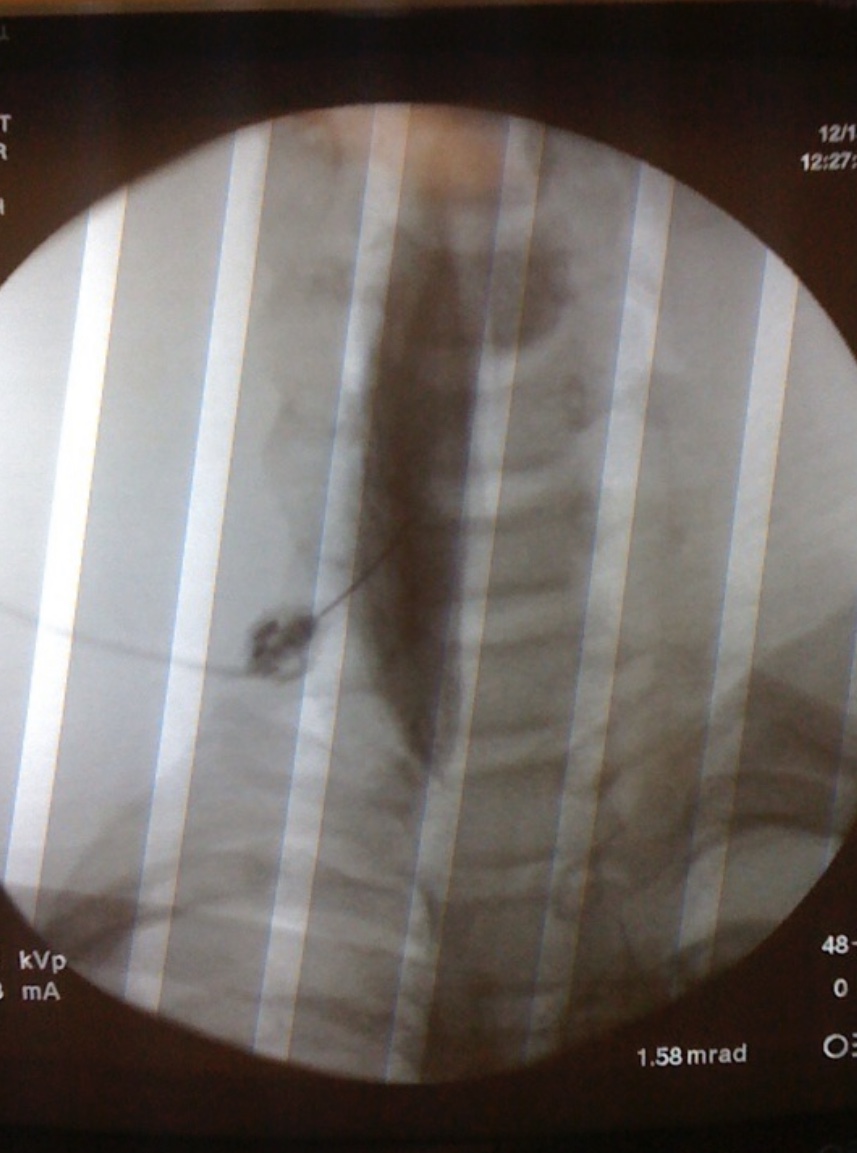

Over time this fracture triggered an inappropriate nerve response in my arm. I began to process any kind of stimulation as unsurmountable pain. The soft cast that was protecting my fracture made me feel like I had third degree burns, the wind felt like a knife slicing off my fingers, and the center of my wrist felt the pressure of an enormous elephant stomping on it. After a few trips to the emergency room I was finally properly diagnosed with CRPS and immediately hospitalized for pain management. This disease wasn’t life threatening, which I am eternally grateful for. However, it was earth-shaking and life-altering to my 16 year old high school self.

I found myself in a wheelchair, unable to walk, unable to use my right arm at all, and worst of all, unable to dance. I was soon transferred to Lucile Packard Children’s Hospital where I met Dr. Elliot Krane. Dr. Krane said I was the worst case of CRPS that he had ever seen. He created a pain rehabilitation program centered around my case, a program that to this day is treating children like me. Through intense physical, occupational, and neurocognitive rehabilitation, we were able to retrain my nerve cells to stop processing stimuli incorrectly. This was the hardest part of my life to date. The pain was unimaginable and the only treatment was to move my arm more, use it more, and touch it more. This unleashed cognitive strength that I didn’t know I had. I was hospitalized for a year and finished my senior year of high school through the hospital school. This was easily the lowest point in my life but what it gave me is my calling.